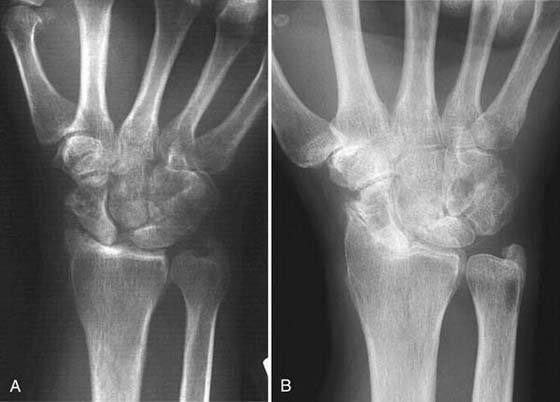

Four-Bone Arthrodesis

Watson and Ballet21 described the scapholunate advanced collapse (SLAC) deformity arising from chronic scapholunate instability. The scaphoid rotates, the capitate pushes in between the scaphoid and lunate, and degeneration occurs first at the scaphoid radial styloid joint (Fig. 76-4A) and then at the capitate lunate joint (see Fig. 76-4B). The radiolunate joint is spared and maintains good articular cartilage in most patients. Pain occurs from degenerative arthritis at the radial scaphoid and capitate lunate joints. For surgical treatment to succeed, this pathology must be addressed. The four-bone arthrodesis procedure removes the scaphoid to eliminate this focus of degeneration and fuses the lunate, capitate, hamate, and triquetrum to stabilize the wrist (Fig. 76-5B, online). This choice of intercarpal fusion prevents further capitate migration. It eliminates the midcarpal degeneration between the capitate and lunate and maintains carpal height. This fusion is also indicated in patients with radiocarpal arthritis from scaphoid nonunion and scaphoid AVN.

images

Figure 76-4 A, Scapholunate advanced collapse (SLAC) wrist. Note arthritis at scaphoid radial styloid joint. B, Severe SLAC wrist. Lunate radius joint is spared from arthritic involvement.